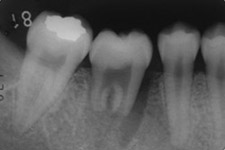

治療前のレントゲンの様子

移植直後。歯根がまだ完成していない歯では、根の先が開いていることに気づきます。